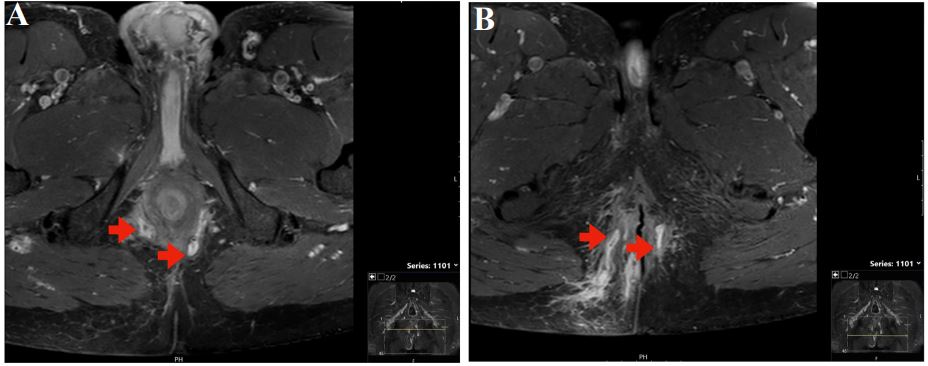

In 2017, a gentleman in his fifties presents to our unit for the management of fistulizing CD. Past medical history is remarkable for a partial small intestinal resection in his twenties, with the macroscopic and histological diagnosis of CD. Due to a mild course of CD, the patient has remained without medical therapy for many years. Unfortunately, there are no preliminary reports from this time, including endoscopies. In 2017, the patient becomes increasingly symptomatic with complex perianal, perirectal, and transsphincteric fistulas. From April to August 2017, the fistulas are drained surgically several times, and Setons are inserted. A colonoscopy in September 2017 showed several fibrin-covered ulcerations and an impassable inflammatory stenosis in the area of the ileocolostomy. In November 2017, immunosuppressive therapy with infliximab (Remicade®) at 400 mg (4 mg/kg body weight) is started with the second dose after 2 weeks, the third after 4 weeks, and then every 2 months [1]. Following our guidance, the patient stopped his long-standing smoking habit in 2019 [9]. After 1 year of infliximab treatment, anti-drug antibodies are detected (Figure 1A), and the therapy is switched to adalimumab (Humira®) [10]. However, due to more pain and secretion from the fistulae, the therapy is switched back to infliximab (Inflectra®) starting with 500 mg (5 mg/kg body weight) at weeks 0, 2, and then every 6 weeks. Low trough levels (0.6 µg/ ml) prompt an increase in dosage at a shorter interval (800 mg, 8 mg/kg body weight every 4 weeks). Because the patient remains symptomatic with purulent secretions from the fistulas, 100 mg/d azathioprine (Imurek®) is added to the therapeutic regimen in December 2019 [11]. Three months later, in March 2020, sigmoidoscopy shows no macroscopic signs of inflammation in the sigmoideum, a mild edematous proctitis and slightly reddened pseudo-polypoid elevations at the anocutaneous line, without recognizable fistula openings. Infliximab trough levels are now in the supratherapeutic range (20 µg/ml) with no detectable anti-drug antibodies. Fistula activity made surgical drainage and Seton insertion necessary in March and May 2020 (Figures 2A + B with pelvic MRI 04/2020). In September 2020, the patient develops Escherichia coli bacteremia and herpes zoster reactivation (shingles) and azathioprine is stopped. In the following 14 months, the patient remains in clinical remission, with continuing subtherapeutic infliximab levels (Figure 1A+B). In December 2021, the patient develops left-sided renal colic and a CT scan reveals urolithiasis and urinary outflow obstruction, and a double J stent catheter is inserted. In January 2022, cystoscopy with flushing cytology leads to the diagnosis of urothelial carcinoma, which is surgically removed by Transurethral Resection of the Urinary Bladder (TURB). Immunosuppression with infliximab is stopped before the operation. In February 2022, a follow-up resection is performed for stage T1 disease. Adjuvant therapy with Bacillus Calmette-Guérin (BCG) installations is started in March 2022 with plans to continue the therapy for 1-3 years. To avoid interferences with the adjuvant BCG immunotherapy, infliximab is not restarted and we decided against the use of other immunosuppressive therapeutic options. A colonoscopy in March 2022 shows a macroscopic (neo) terminal ileitis with evidence of multiple elongated fibrinous ulcerations in the distal 10 cm of the neoterminal ileum and substenosis in the area of the inflamed ileo-colostomy. Perianal Fistula orifices are visible in distal rectum and proximal anal canal inactive at time of examination (Figures 3A+B). Clinical the patient was still in remission. In April 2022, we start CDED with PEN using a nutritional formula (Modulen®) [12-14]. The patient has been able to integrate the diet well into his daily routine. In October 2023, at the time of writing, 18 months after the start of CDED and PEN, he reports normal stool consistency and frequency with two daily bowel movements. The fistulas continue to secrete blood and pus, but without pain or the need for antibiotics. Surgery and antibiotic treatment for fistulas had last been necessary in June 2022, respectively. CD remission under CDED with PEN was confirmed by a low CRP value (6-11 mg/L, normal range <5 mg/ L, see Figure 1A). Similarly, the Crohn’s Disease Activity Index (CDAI) is at 20 points (Figure 1A), indicating persistent clinical remission. A control endoscopy has not yet taken place.

Figure 2A+B: Perianal fistulas (red arrows) in MRI of the pelvis in 04/2020.